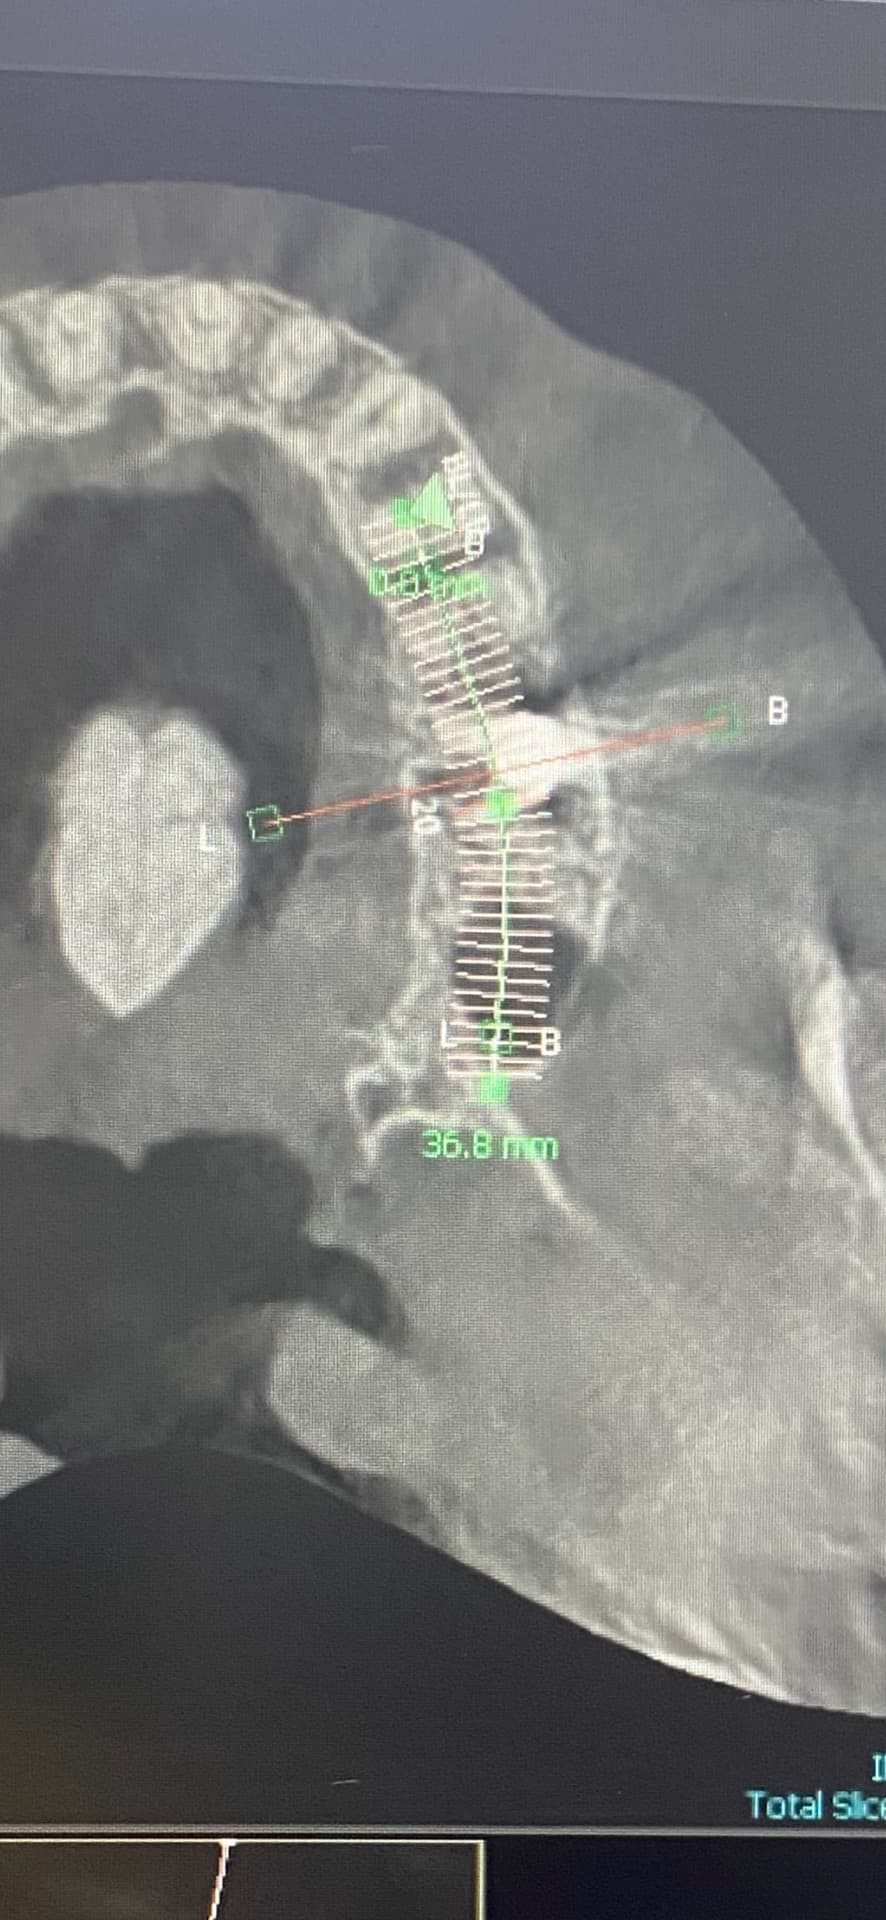

치우쳐 있는 임플란트 시간이 지나도 갠찮을까요?

지금 볼쪽으로 치우쳐잇어서 불편해서 보철 올렷다가 뺏어요, 볼쪽 잇몸이 염증이 생겨서 불편한데 보철로 커버 할수 잇다고 해서 이번에 보철 올리고도 불편한지 보자고 하거든여 ㅠ

임플란트를 할 때는 임플란트 뿌리가 잘 지지될 수 있는 치조골 안에 임플란트를 식립 하게 됩니다. 임플란트의 위치가 바깥으로 살짝 나와 있다고 하더라도 보철을 하게 되면 비정상적인 위치를 맞춰주게 됩니다.

임플란트 위치가 중요하긴 하지만, 많이 치우친건 아닌거 같으니 보철물을 잘 만들어서 사용하시면괜찮을것같습니다.